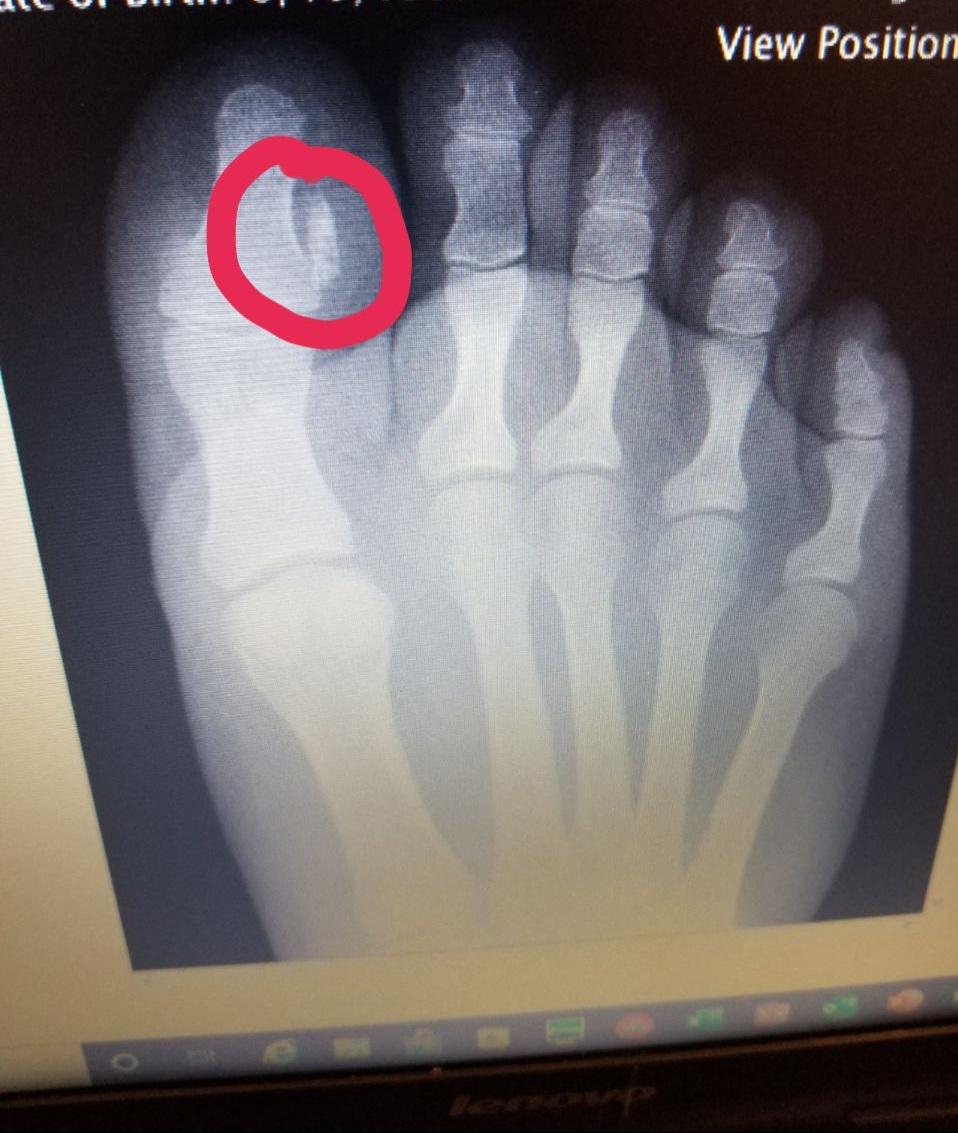

Bone Spur Under Big Toe Nail (Subungual Exostosis) YouTube Is A Nail Bone A nail is a hard, keratinized structure found at the tips of the fingers and toes in humans and many other animals. The nail unit consists of: The nail itself, the underlying structure that supports nail growth, and the skin tissue that surrounds it. Nail anatomy includes the nail plate, nail bed, and surrounding tissue. Nails are made of dead. Is A Nail Bone.